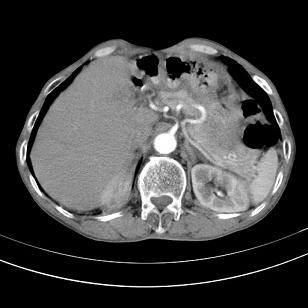

标题: 男,65岁,反复右上腹痛, [打印本页]

标题: 男,65岁,反复右上腹痛,

胃镜提示十二指肠占位